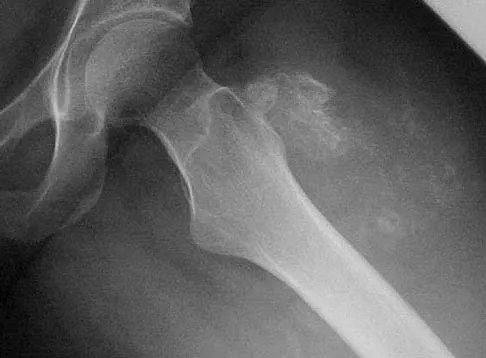

A 35-year-old patient has right hip pain. Figures 34a and 34b show the coronal MRI scan and the biopsy specimen. What is the most likely diagnosis?

Explanation

Alcohol abuse, steroids, Caisson disease, sickle cell disease, and radiation therapy are the leading causes of nontraumatic osteonecrosis of the femoral head. Arlet J: Nontraumatic avascular necrosis of the femoral head: Past, present, and future. Clin Orthop 1992;277:12-21.